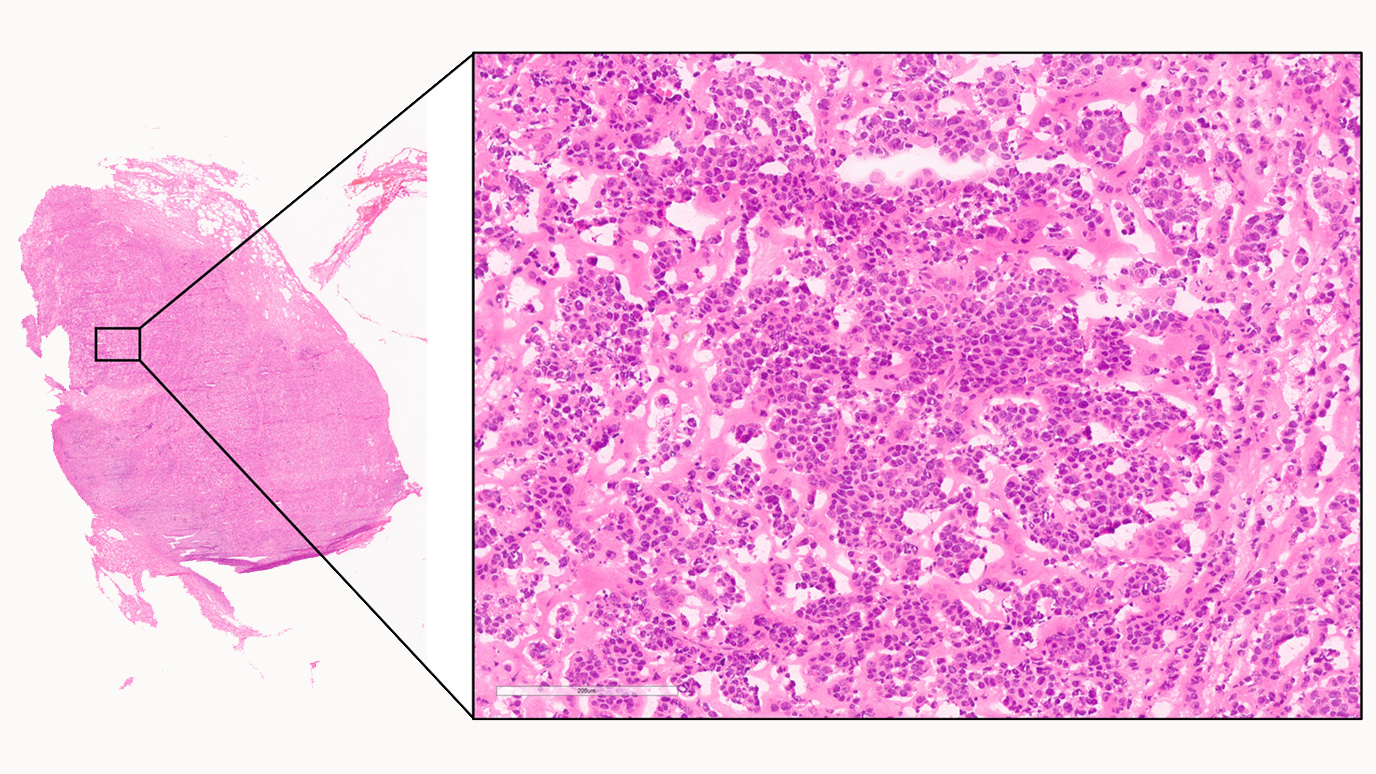

Mutational signature profiling classifies subtypes of

Mutational signature profiling classifies subtypes of